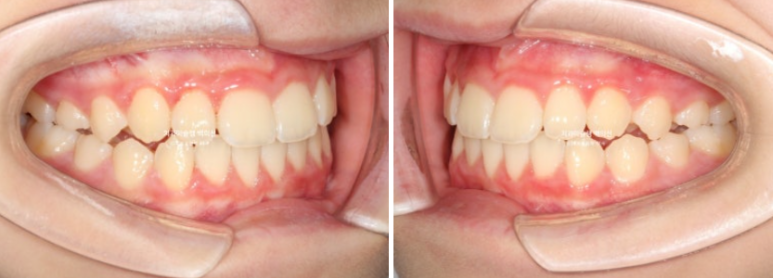

23.06~25.06

남아있는 유치는 없고 완전한 영구치열에 접어들었습니다.

처음에 비해 무턱을 나타내는 수치가 6.4에서 4.7로 줄어들었습니다

4.7은 이 나이대에서는 정상범위 입니다.